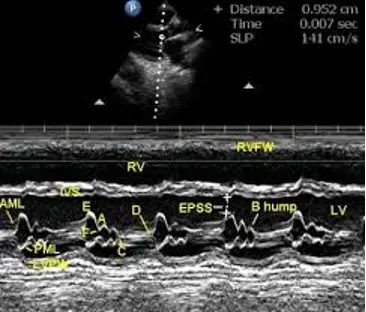

B-bump

B-bump on M-mode indicates elevated LVEDP